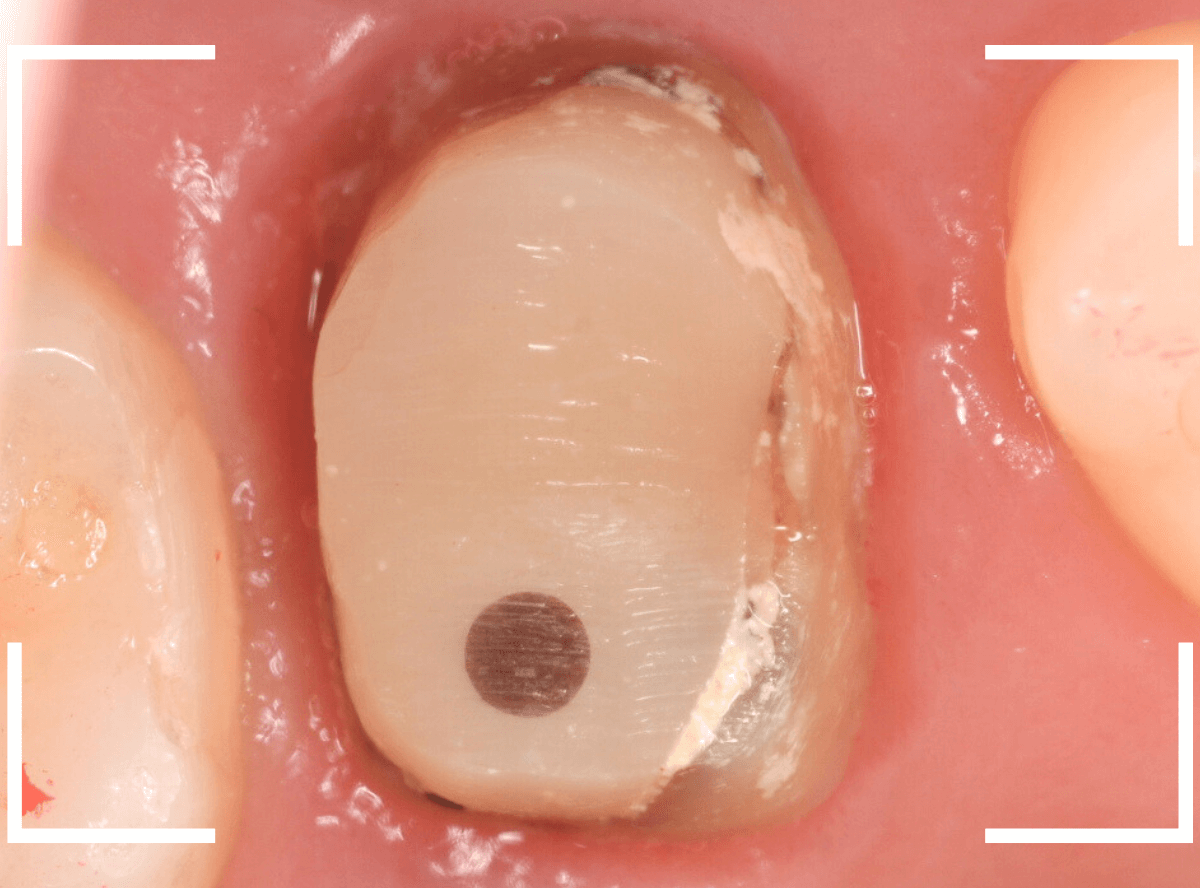

さし歯の土台の補修と、おやしらずの虫歯の処置をしたところです。

この状態で型をとります。